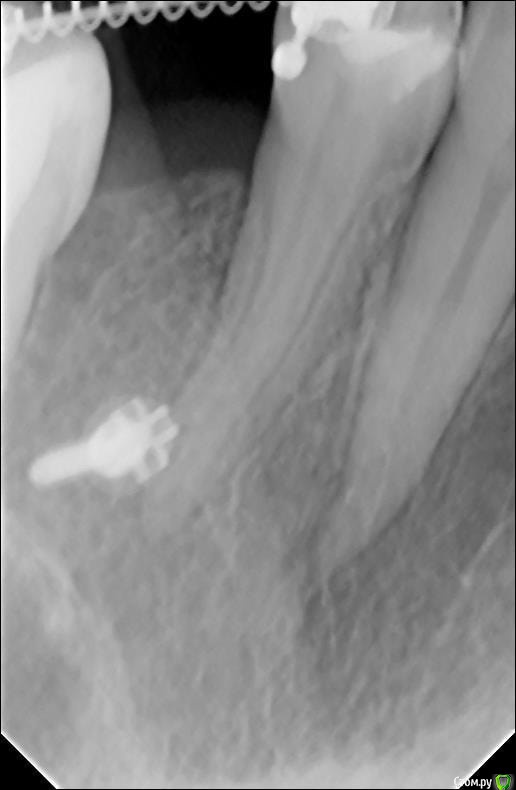

tatsiana.ma Опубликовано 27 февраля, 2019 Поделиться Опубликовано 27 февраля, 2019 (изменено) Здравствуйте. Предыстория: 25 зуб - первичная адентия, молочный был удален очень рано в 11-12 лет, место не сохраняли. Сейчас мне 35 лет, по плану получение места для имплантации отсутствующего 25-го зуба.На данный момент прохожу лечение у ортодонта. Необходима интрузия 6-ки и под это дело установка ортодонтического миниимпланта нёбно в области 25 (ближе к 26). Для установки миниимпланта ортодонт отправил к хирургу, хирург начал противиться, мол, установим сейчас винт, под нагрузкой начнется воспалительный процесс в кости и резорбция, что в последующем может помешать установить уже ортопедическоий имплант на место 25-го. Хочу поинтересоваться вашим мнением, так ли все грустно и реальна ли предполагаемая ситуация? Неужели мини имплант может оставить после себя такие разрушительные последствия в кости? Второй снимок - свежий. Изменено 27 февраля, 2019 пользователем tatsiana.ma Ссылка на комментарий

red_butler Опубликовано 5 марта, 2019 Поделиться Опубликовано 5 марта, 2019 К сожалению качественные фото не получились. Да я и другого хирурга нашла, который установил мне микроимплант. винт.jpegНа снимке все хорошо. ортодонту для интрузии одного ортоимпланта хватит? Ссылка на комментарий

Brigita Опубликовано 5 марта, 2019 Поделиться Опубликовано 5 марта, 2019 мол, установим сейчас винт, под нагрузкой начнется воспалительный процесс в кости и резорбция, что в последующем может помешать установить уже ортопедическоий имплант на место 25-го. Хочу поинтересоваться вашим мнением, так ли все грустно и реальна ли предполагаемая ситуация? Неужели мини имплант может оставить после себя такие разрушительные последствия в кости? орто.pngВторой снимок - свежий.как правило такого не происходит. Ссылка на комментарий